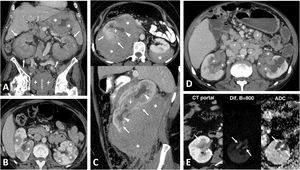

PTEN syndrome-associated clear cell renal cell carcinoma (ccRCC). (A–D) PTEN syndrome. (A) Axial CT scan of the abdomen in the nephrographic phase. (B) Transverse section of ultrasound in B-mode of right hypochondrium. (C) Coronal cervical CT. (D) Photograph of the forehead. An 81-year-old male with haematuria. Physical examination revealed macrocephaly, a mass located at the base of the right side of the cervical region and evident papillomatous facial lesions (D). Imaging studies show several focal right renal lesions with intense enhancement and areas of necrosis (arrows). The largest of these is accompanied by a tumour thrombus, grade 4 in the Mayo clinic classification, which is echogenic and uptakes contrast (*). In addition, a large enhancing mass is visible near the right thyroid lobe (hollow arrows in C). A core needle biopsy was performed on the principal renal mass, which was diagnosed as ccRCC, and on the thyroid mass, which was diagnosed as follicular thyroid cancer, the most frequent histological subtype in this syndrome. The patient died before genetic testing was carried out, but they met the criteria for PTEN syndrome. (E) PTEN syndrome simulator. Coronal CT in nephrographic phase. A 79-year-old female. Lobulated renal mass with intense enhancement and central necrosis (arrows) together with a similar mass near the left thyroid lobe. While PTEN syndrome was suspected, the histological diagnosis was ccRCC with thyroid metastasis. The patient did not meet any other clinical criteria for PTEN.

Hereditary papillary renal cell carcinoma (pRCC) in a 74-year-old male. Incidental finding. (A) (coronal) and (B) (axial; composite image). CT in nephrographic phase. Exophytic right renal cystic mass (arrows) with a solid nodule hypoattenuating with respect to the renal parenchyma (arrowheads). There is also an exophytic cortical mass, which is also hypoattenuating, near the contralateral kidney (*). A core needle biopsy of the solid component of the right solid nodule was performed, revealing a pRCC, and so percutaneous radiofrequency thermoablation was performed in the same procedure. (C) Coronal CT in the nephrographic phase one day after ablation. Loss of tension in the right cystic component (arrow) and small residual attenuating image (arrowhead), without enhancement compared to the non-contrast study (not shown). The contralateral lesion (*) showed absolute enhancement of 32 HU and was also suspected to be a pRCC. The urology department decided to perform a left nephrectomy, which confirmed this suspicion. In addition, numerous millimetric papillary adenomas were identified in the left kidney. (D) Axial CT (composite image) without contrast (due to renal failure) five years after nephrectomy. Image showing no recurrence in the right kidney (dashed arrow) and left nephrectomy (hollow arrow).

Papillary thyroid carcinoma and papillary renal neoplasia in a 32-year-old female. Palpable enlarged lymph nodes in the neck. (A) B-mode ultrasound of the left thyroid lobe and qualitative strain elastography of the cervical lymph node. (B) Cervical CT (axial and coronal) with intravenous contrast. Hypoattenuating nodular lesion measuring 21 mm with microcalcifications in the left thyroid lobe (hollow arrows) and laterocervical lymphadenopathies, also with microcalcifications and tissue stiffness on qualitative elastography. The histological result after surgical resection was papillary carcinoma with lymph node metastases. (C) CT at the level of the left kidney, without contrast, in the corticomedullary phase and in the nephrographic phase. (D) Non-contrast ultrasound. Axial image captured 55 seconds after contrast administration. Exophytic cortical solid nodular lesion in the left kidney that was slightly hyperattenuating in the baseline study, and discreet enhancement that even raised the possibility of pseudoenhancement on CT (ROI), better seen on contrast-enhanced ultrasound (*), where intralesional ‘bubbles’ could be observed in real time. A partial nephrectomy was performed, which resulted in a diagnosis of papillary renal cell carcinoma. There was no familial aggregation, and no genetic testing was carried out.

Birt-Hogg-Dubé syndrome. A 68-year-old male. Incidental finding in an ultrasound examination. (A) Ultrasound centred on a lesion. In B-mode (arrow) it is discreetly hypoechogenic, with contrast enhancement (red ROI), purely intravascular, almost as intense as that of the renal parenchyma (yellow ROI), both in the static image and in the time-intensity curve (not shown). Core needle biopsy was performed on this lesion and on another lesion (not shown), with histological diagnoses of a chromophobe cell renal carcinoma and an oncocytic lesion. (B) CT Multiple focal bilateral renal lesions of various sizes and well demarcated (at least six were identified) with moderate enhancement, somewhat weaker than that of the renal parenchyma and more intense in the corticomedullary phase (arrows). One had some small focal calcification (not shown). Thin-walled cysts are also visible at the lung bases (arrowheads). (C) MRI centred on the larger lesion (arrows). It shows signal intensity in T1 (similar for in-phase and opposed-phase sequences) and T2, as well as moderate water diffusion restriction, with an average ADC value of 0.91 × 10−3 mm2/s and clearly less intense enhancement than that of the renal parenchyma in the time-intensity curve (ROI and red and yellow curves, respectively). The genetic study confirmed a germline mutation of the FLCN gene in heterozygosis.